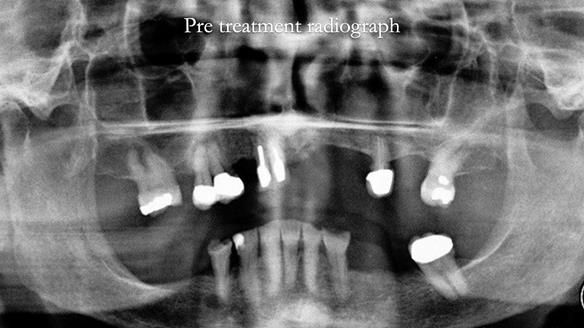

- Upper and lower metal based RPDs, poorly fitting, worn occlusal surface, reverse curve aesthetics, lacking support

- The upper right central and lateral incisors with post crowns. Healthy and functionally secure but with poor appearance, contributing to the reverse curve.

- Moderate to heavily restored dentition with deep overbite (Class 2 div II)